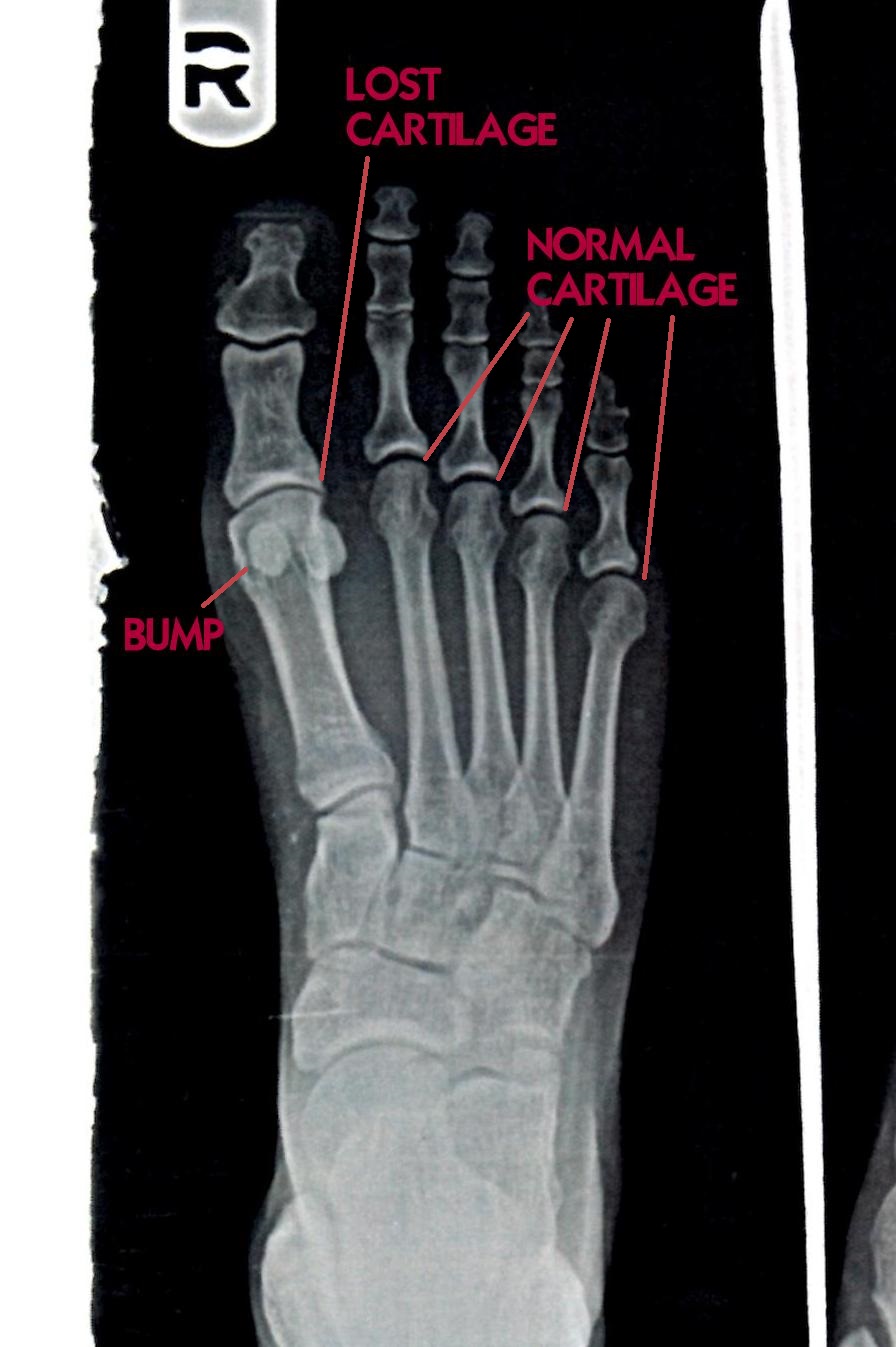

Does Hallux Rigidus Go Away . Hallux rigidus causes pain, stiffness and bone spurs to form on the top of your big toe joint. Hallux (big toe) rigidus (rigid) is a condition where your big toe’s range of motion is severely limited or completely frozen due to. Hallux rigidus is more common in females. A hard bump at the top of the foot. An inability to move the big toe. Treatment for hallux rigidus usually involves a combination. Cheilectomy is surgery to remove bone spurs. Hallux rigidus (stiff big toe) hallux rigidus (stiff big toe) occurs when the joint at the base of the big toe stiffens. It is the most common arthritic condition in the foot and can make. In hallux rigidus, osteoarthritis breaks down the cartilage covering the ends of the bones that make up. Symptoms of cystic bone changes and bone or joint damage related to hallux rigidus include: Constant, persistent pain that is felt even during rest. Hallux rigidus symptoms usually include stiffness and pain in the big toe, swelling, difficulty walking and corns and calluses. Limping due to pain and changing the way you walk to reduce pain.

Hallux rigidus symptoms usually include stiffness and pain in the big toe, swelling, difficulty walking and corns and calluses. An inability to move the big toe. Treatment for hallux rigidus usually involves a combination. Constant, persistent pain that is felt even during rest. It is the most common arthritic condition in the foot and can make. Cheilectomy is surgery to remove bone spurs. Limping due to pain and changing the way you walk to reduce pain. Hallux rigidus causes pain, stiffness and bone spurs to form on the top of your big toe joint. Hallux rigidus is more common in females. Symptoms of cystic bone changes and bone or joint damage related to hallux rigidus include: